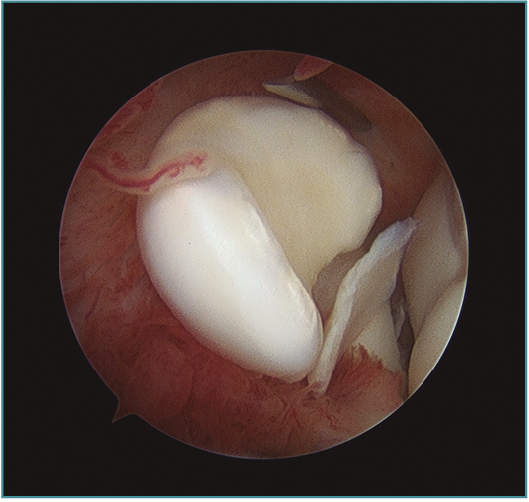

Los portales más adecuados son el anteromedial proximal para la óptica y el anterolateral, el anterolateral proximal y el mediolateral directo o soft-spot (Figura 4) como portales de trabajo. Los portales anteromediales permiten una excelente visualización de la cámara anterior, de la superficie articular de la cabeza radial, del cóndilo humeral, de la apófisis coronoides y de la cápsula anterior y lateral (Figura 5). A este nivel suelen observarse la gran mayoría de los cuerpos libres articulares que en ocasiones se encuentran en la zona lateral y posterior del codo (Figura 6).

Figura 5. Imagen artroscópica de defecto condral en porción anteroinferior de capitellum. Óptica en portal anteromedial proximal.

Figura 6. Abundante sinovitis y cuerpo libre alojado en cámara anterior en un paciente con lesión osteocondral de tipo IV de la International Cartilage Repair Society (ICRS).